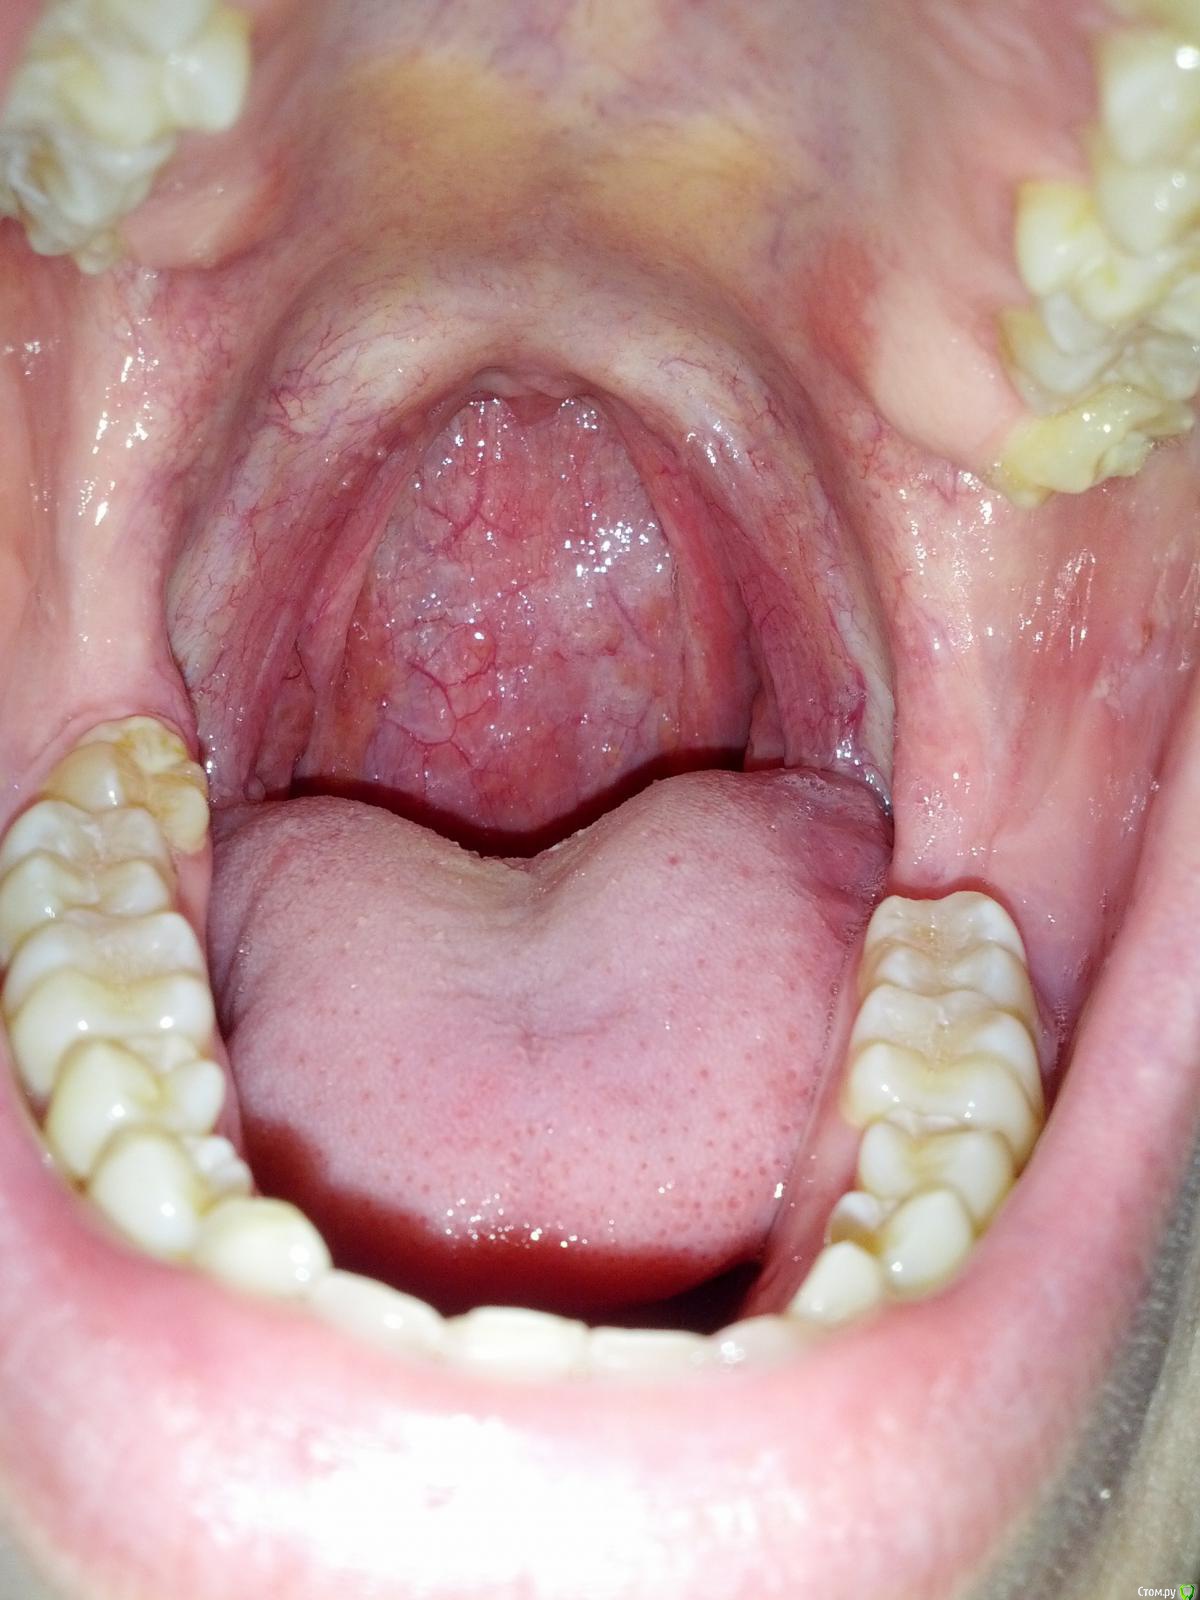

Давно заметил в ротовой полости белую слизь.. Без фонарика она видна только слева и справа (не гланды, а перед ними. На фото видно). Пальцом она не снимается. Сегодня сделал фото при ярком освещении и загрустил сильнее.. Еще заметил Какой-то желтоватый налет на верхнем небе и белая слизь видна во многих местах.

Вот уже пару месяцев чувство скопления слизи в горле, отчего хочется периодически схаркивать и плеваться. Кашля и насморка нет. Вредных привычек нет. На вкус слизь соленая и беловатого цвета (иногда желтоватого)

Стрелочками на третьей фото отметил налет, который виден даже в плохом освещении. Повторюсь, пальцами оне соскабливается..